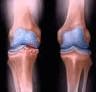

آرتروز شایع ترین نوع آرتریت در انگلیس به شمار می رود. آرتروز یا استئوآرتریت (osteoarthritis) شایع ترین بیماری از دسته التهاب مفاصل است.

در این بیماری غضروف مفصل صدمه دیده و کم کم از بین می رود؛ آرتروز ممکن است هر مفصلی را درگیر کند اما مفاصل بزرگ که وزن بدن را تحمل می کنند مثل مفاصل زانو و ران و ستون فقرات بیشتر در معرض ابتلا هستند.

زانوها از آسیب پذیرترین مفاصلی هستند که تحت تاثیر این بیماری قرار می گیرند بطوریکه از هر پنج بزرگسال بالای ۴۵ سال یک نفر به درد زانوی ناشی از آرتروز مبتلا است.